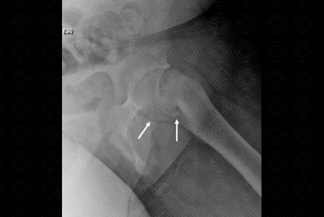

Texto alternativo para a imagem Figura 2. Créditos: Dra. Elazir Mota - Rio de Janeiro/RJ

Descrição da figura 2: Na incidência em Lowenstein ou posição da rã observa-se nitidamente o deslocamento posterior da epífise femoral em relação à metáfise esquerda (setas brancas). A incidência em Lowenstein é muito importante diante da suspeita diagnóstica de epifisiólise.

• Radiografia da bacia em AP e Lowenstein: A incidência em Lowenstein (ou posição da rã) é essencial nestes pacientes, por ser mais sensível na detecção das alterações iniciais do deslizamento epifisário. Por isso, deve ser rotina básica na avaliação radiológica dos adolescentes que se apresentem com claudicação ou dor no joelho/quadril. Observa-se que nestes pacienes acometidos, a epífise escorrega posterior e medialmente (figuras 1 e 2);